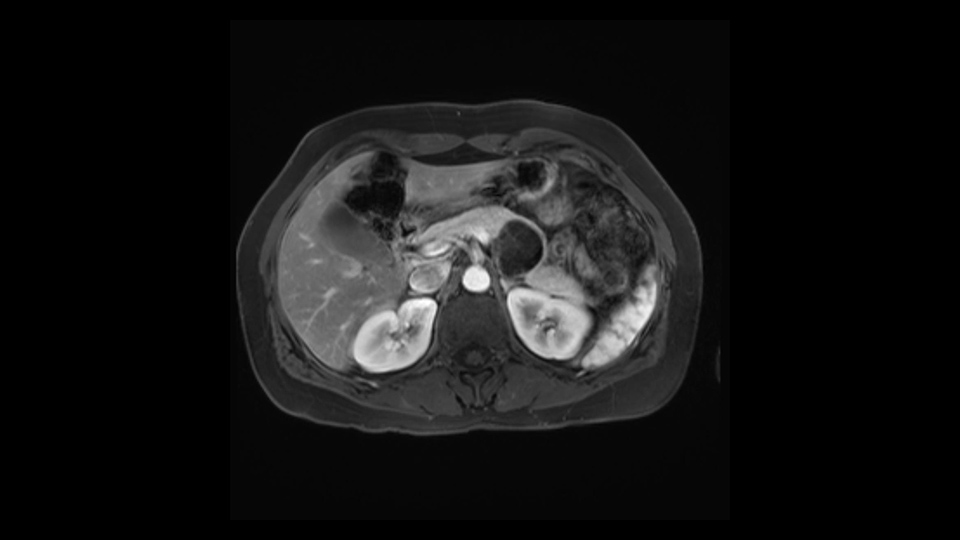

In reviewing this patient’s CT scan, first of all, the lesion is again cystic with a very thin wall. I anticipate that it will be delicate and potentially friable. And therefore the risk of rupture exists and we need to be very careful in how we handle the pancreas and the tumor throughout the procedure.

In light of these findings, on the cross sectional imaging which include MRI, our plan would be to perform a laparoscopic distal pancreatectomy. I think based on oncologic grounds, a spleen preserving procedure is probably reasonable. From looking at the scan, its likely technically possible although a vessel preserving procedure is likely not appropriate for this patient. Technical intraoperative factors will certainly influence that decision.

Hi my name is Carol-anne Moulton, I’m one of the surgeons here at TGH and an associate professor in the department of surgery. So I’ve had the ability to look at the MRI of this case that I’ve been asked to comment on. It has a mucinous or what appears to be a mucinous cystadenoma in the tail of the pancreas. To me, it looks like a pretty straightforward case. I agree with the decision to remove the tumor or cyst, give that it is unilocular and large and likely a mucinous cystadenoma. My preferred method of doing this particularly in a benign situation would be a laparoscopic distal pancreatectomy with or without the spleen.

The preoperative MR is very very important; any scan for that matter. Whether it is a pancreatic protocol CT scan or the MR as presented, the diagnostic imaging plays a very big role. And with this we see that it’s a very well-defined cystic focus in the body of the pancreas. Although there are septal enhancements, very well demarcated, but there is no vascular involvement. However, the mass appears to be in contact with the splenic vessel, and the mass is also a little bit in touch with the left adrenal and also the loop of bowel. So looking at this, basing on the features, I think it’s probably a mucinous cystic lesion, it could possibly be a pseudocyst. But basing on the history, it appears like there is no history that would point out to a pseudocyst. And not an IPMN as well; I don’t see any side branches from the MRCP and the MR scan and although there is no axial T2 images available, and I truly find it easier to identify the septations on T2, and the hepatic cyst that is visible on this scan makes it hard to differentiate it from a simple or complex cyst which may be considered in a mucinous neoplasm with cystic or mucinous metastasis. Basically the contrast would help us in identifying the enhancing mural nodules or septations in the cysts. The MRCP is definitely helpful to identify if there is any side branch, if we are considering any IPMN.

So first, I'll show you the scan. Here's the traditional view, where you see the cyst, which is in the body of the pancreas. And you see over here, it's got a quite thick wall. And going a little bit back also, here you see a septation which is very important, because I think a septation is what separates this from, for instance, the pseudocyst of the pancreatitis. And also the location of the cyst you see here, abutting the adrenal gland and going down a bit more, it's also quite close to a bowel loop. So when thinking about this cyst: female, the location in the body of the pancreas, thick wall, septation, and as you can read in history, it was basically asymptomatic, so no signs of pancreatitis. So, this probably all points towards a mucinous cystic neoplasm.